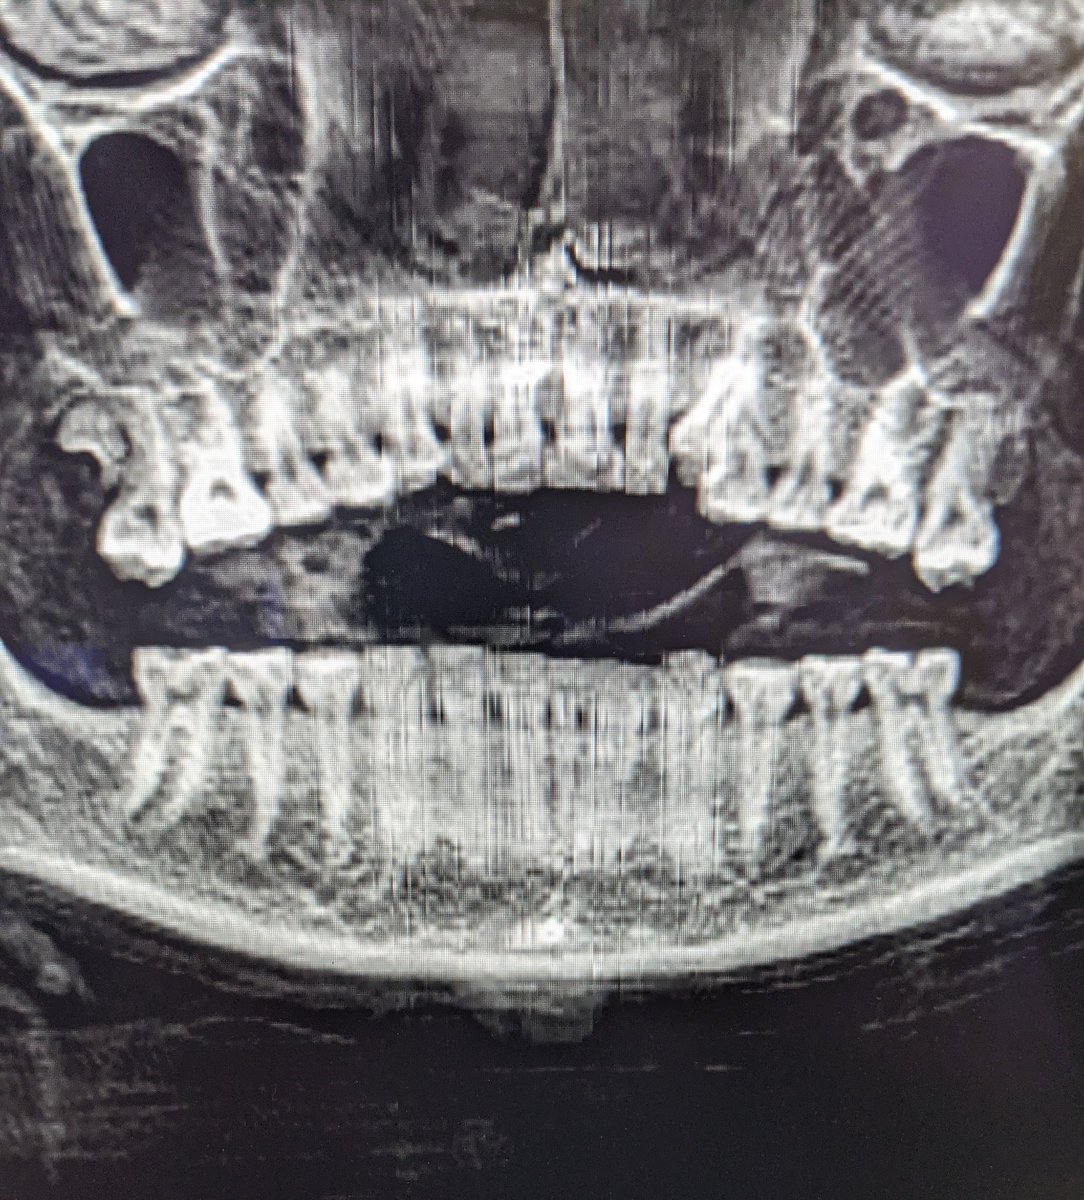

Comme c'est une question qui est revenue plusieurs fois, pour la team dentaire je vous ai fait une reconstruction curviligne épaisse qui montre en effet des dents en plutôt bon état ! 😉 Image